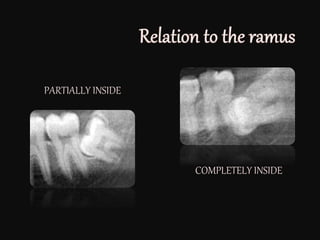

PARTIALLY INSIDE

COMPLETELY INSIDE